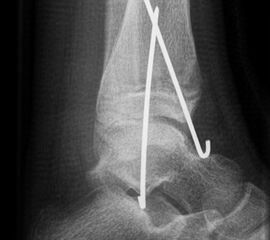

Fugengelenkfrakturen treten typischerweise vor dem 10. Lebensjahr auf, in einer Phase, in welcher die Wachstumsfugen noch weit offen sind. Dieser Frakturtyp betrifft fast ausschließlich den medialen Malleolus. Laterale Frakturen sind extrem selten, teilweise kommt es zu lateralen Bandverletzungen oder Fugenschaftfrakturen der distalen Fibula. Die Frakturlinie verläuft in einer Verlängerungslinie von der medialen Taluskante nach proximal. Häufig stellen sich Verletzungen des Innenknöchels im Röntgenbild schlechter dar, insbesondere wenn die Aufnahmen verdreht sind oder die Ebene der Fraktur bei geringer Dislokation verkippt zur Röntgenebene liegt. Besteht klinisch der geringste Hinweis auf eine Verletzung des Innenknöchels, muss aufgrund der Tragweite der Verletzung durch entsprechende Aufnahmen gegebenenfalls auch Schnittbildverfahren die Verletzung sicher diagnostiziert oder ausgeschlossen werden (Abb. 15).

„Kadiläsion“- Mediale Malleolarfraktur

Bei kindlichen Verletzungen des medialen Malleolus handelt es sich nach L. v. Laer um eine sogenannte Kadiläsion, d.h. eine Verletzung mit hohem Risiko eines schlechten Behandlungsergebnisses bei nicht korrekter Behandlung. Selbst bei optimaler Therapie ist das Risiko für spätere Wachstumsstörungen hoch, sodass diese Verletzungen nicht selten ein juristisches Nachspiel haben. Durch die Verletzung der wachstumsaktiven Zone kann es zu einem vorzeitigen Verschluss der Wachstumsfuge kommen, mit entsprechendem Fehlwachstum. Das Risiko eines vorzeitigen Verschlusses der Wachstumsfuge korreliert mit dem Ausmaß der Schädigung der wachstumsaktiven Zone. Ab dem 13. Lebensjahr wird das Risiko bei reduzierter Wachstumsaktivität zunehmend geringer.

Fugengelenkfrakturen können die Wachstumsfuge durchkreuzen (Abbildung 16a), ohne oder nur mit minimaler Beteiligung der Fuge sehr weit medial liegen (Abbildung 16b) oder durch die Fuge auslaufen (Abbildung 16c). Relevant für die Wachstumsprognose ist weniger die Form der Fraktur, sondern das Alter des Patienten zum Zeitpunkt des Traumas sowie das Ausmaß der Schädigung der Wachstumsfuge, wobei eine Korrelation mit dem Ausmaß der Dislokation besteht.

THERAPIE

Behandlungsziel ist die exakte Rekonstruktion der Gelenkfläche sowie die Minimierung des Risikos einer späteren Wachstumsstörung. Dislozierte Frakturen werden offen reponiert, die Osteosynthese erfolgt mit einer Kleinfragmentschraube. Finden sich viele kleine Fragmente kann eine K-Draht Osteosynthese durchgeführt werden. Wird der Innenknöchel operiert, kann bei gleichzeitiger hochgradiger lateraler Instabilität eine Rekonstruktion des lateralen Bandapparats durchgeführt werden. Fibula Frakturen stellen sich meist spontan ein, sodass hier keine zusätzliche Osteosynthese notwendig ist.

Nach der Osteosynthese wird die Fraktur für ca. vier Wochen in einem Unterschenkelgips ruhiggestellt. Bei Schmerzfreiheit der Frakturzone erfolgt anschließend eine schmerzadaptierte Belastungssteigerung über weitere zwei Wochen. Sobald unter Alltagsbedingungen Beschwerdefreiheit besteht kann die sportliche Belastung langsam gesteigert werden. Kirschnerdrähte werden 6-8 Wochen postoperativ, Schrauben nach zwölf Wochen entfernt. Es empfiehlt sich klinische und radiologische Kontrollen im Abstand von 6 Monaten bis zum Wachstumsabschluss durchzuführen, um ein mögliches Fehlwachstum frühzeitig zu erkennen.